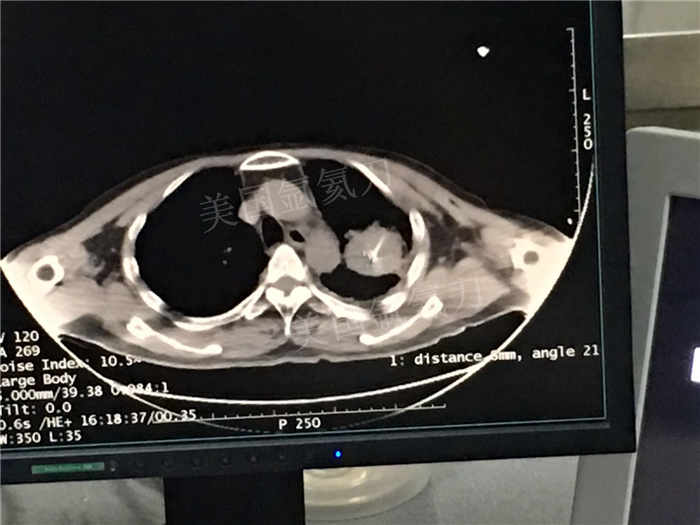

下一篇:中日友好医院氩氦刀冷冻消融治疗胸膜间皮瘤